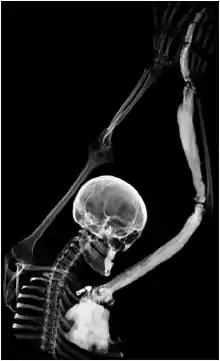

Melorheostosis is a medical developmental disorder and mesenchymal dysplasia in which the bony cortex widens and becomes hyperdense in a sclerotomal distribution. The condition begins in childhood and is characterized by thickening of the bones. Pain is a frequent symptom and the bone can have the appearance of dripping candle wax.[1]

Melorheostosis is a mesenchymal dysplasia manifesting as regions of dripping wax appearance or flowing candle wax appearance.[5] The disorder can be detected by radiograph due to thickening of bony cortex resembling "dripping candle wax." It is included on the spectrum of developmental bone dysplasias including pycnodysostosis and osteopoikilosis.[6] The disorder tends to be unilateral and monostotic (i.e. affecting a single bone), with only one limb typically involved. Cases with involvement of multiple limbs, ribs, and bones in the spine have also been reported. There are no reported cases of involvement of skull or facial bones. Melorheostosis can be associated with pain, physical deformity, skin and circulation problems, contractures, and functional limitation. It is also associated with a benign inner ear dysplasia known as osteosclerosis.[7]